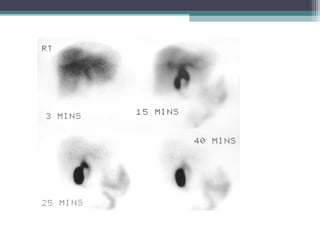

Hepatobiliary scintigraphy

A technetium-labeled iminodiacetic acid

(IDA) analogue is typically used, include99m

Tc (technetium-99m) DISIDA (di

isopropyl-iminodiacetic acid) and99m

Tc

mebrofenin (trimethylbromo-

iminodiacetic acid).

 Infants with biliary atresia usually have

normal hepatocyte uptake of the

radiotracer if they are younger than 2

months of age.

If excretion of radiotracer into the bowel is

seen, biliary atresia is virtually excluded. If

radiotracer excretion is absent after 24

hours (as it is in the image below), biliary

atresia is suspected.